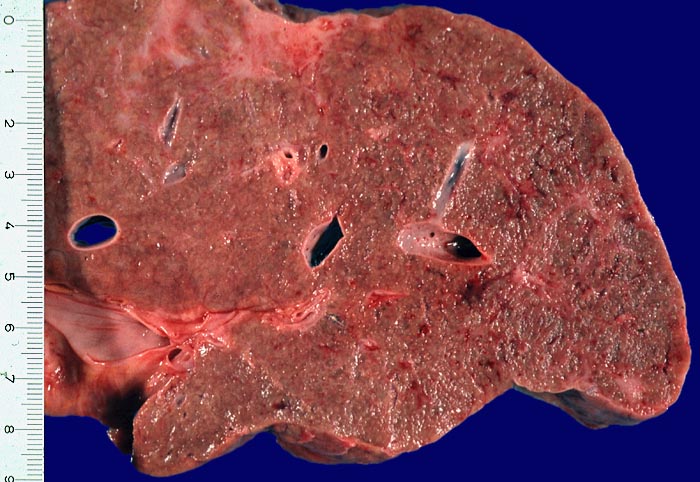

Makroskopie

Befund

Pathologischer Befund

Normalbefund